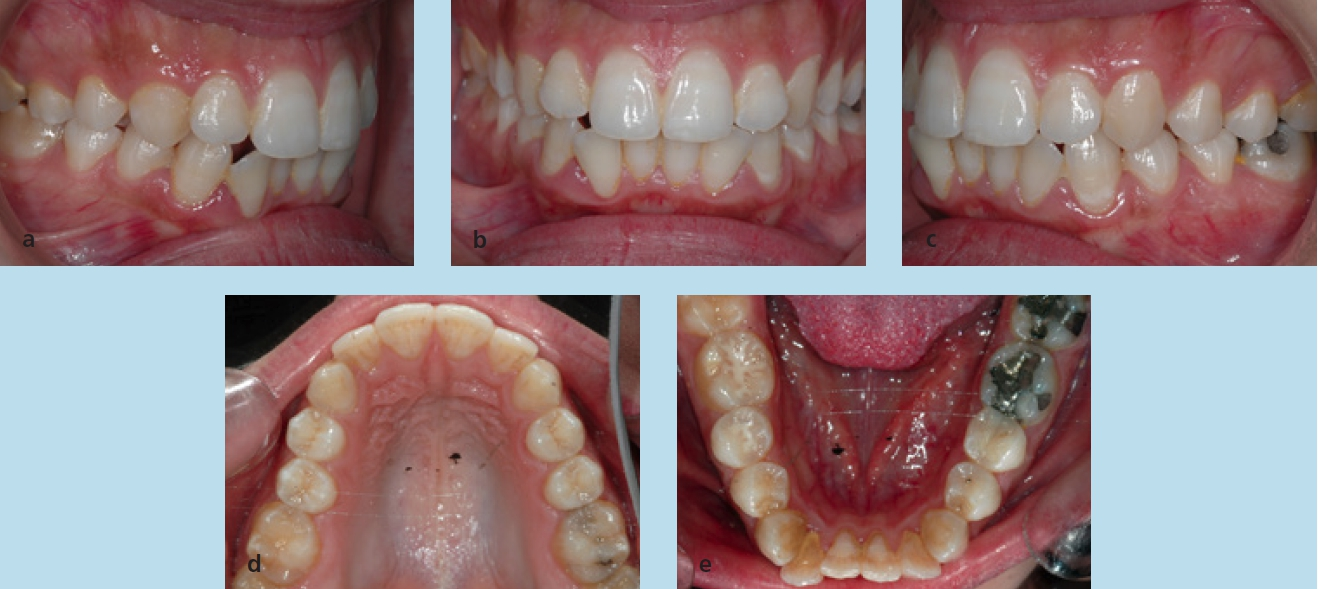

Die Patientin stellte sich im Alter von 23 Jahren zu einer kieferorthopädischen Beratung vor. Sie störten die Engstände im Unterkieferzahnbogen. Die extraoralen Aufnahmen zeigen ein schönes, harmonisches, leicht konvexes Profil, das nach den Grundregeln der Ästhetik nicht verändert werden darf (Abb. 18a bis c). Die intraoralen Aufnahmen zeigten zu Behandlungsbeginn eine Angle-Klasse-I-Okklusion, Tendenz zu Klasse III rechts und Klasse I links. Auf der Frontalaufnahme ist die knappe sagittale und vertikale Frontzahnstufe zu sehen (Abb. 19a bis c). Im Rahmen der Modellanalyse konnte eine harmonische Breitenrelation beider Zahnbögen im Bereich der Molaren und Prämolaren ermittelt werden, im Oberkiefer waren die Platzverhältnisse ausgeglichen. Im Unterkiefer lag ein Engstand von insgesamt 5 mm vor, wobei sich die Engstände auf die Frontzahnregion konzentrierten (Abb. 19d und e). Das angefertigte OPG (Abb. 20) zeigte, dass alle Zähne vorhanden und die Zähne 38 und 48 retiniert und verlagert waren. Im Seitenzahngebiet war eine konservierende Versorgung zu verzeichnen. Die parodontale Situation war röntgenologisch sowie klinisch unauffällig und die Knochenverhältnisse ließen eine orthodontische Behandlung zu. Die Fernröntgenaufnahme (Abb. 21) zeigte keine skelettalen Auffälligkeiten. Die Oberkieferfront stand nahezu achsengerecht, die Unterkieferfront war nach labial gekippt (Tab. 3).

Für die Behandlung und geplanten Zahnbewegungen wurde eine festsitzende Apparatur (0,022 × 0,028 Slot-Brackets) eingegliedert; im Oberkiefer erfolgte eine vollständige Bebänderung, im Unterkiefer nur eine Teilbebänderung der Seitenzähne (Abb. 22a bis c). Aufgrund der Achsenstellung der Fronten im Unterkiefer sollte eine weitere labiale Kippung bei der Auflösung des Engstandes vermieden werden. Um dies weitestgehend umsetzen zu können, wurde im gesamten Frontzahngebiet und bei den seitlichen Zähnen inklusive der Mesialfläche der Unterkiefereckzähne um insgesamt 4 mm gestrippt (0,20 bis 0,25 je Approximalfläche). Die Form der Zähne und der Verlauf der Gingiva ließen dies zu. Zu Beginn der Behandlung wurden nur die 1. Molaren, Prämolaren und Eckzähne bebändert, um die Proklination der unteren Schneidezähne zu vermeiden. Die Prämolaren wurden jeweils von mesial und distal sowie die Eckzähne von distal mit dem oszillierenden EVA-Winkelstück mit Hubbewegung gestrippt. Für eine effektive Distalisation und Ausnutzung des gewonnenen Platzes wurde in den Bogen zwischen den Zähnen 33 und 43 eine Druckfeder eingesetzt (Abb. 23). Nach vollständiger Distalisation der seitlichen Zähne wurden die Schneidezähne beklebt. Vor dem Einligieren des Bogens wurde die Unterkieferfront von mesial und distal einschließlich der mesialen Fläche der Eckzähne gestrippt. Es wurden Lace-backs und voller Bogen eingesetzt (Abb. 24a bis c).

Um die Okklusion in der vertikalen Dimension zu kontrollieren und den knappen Überbiss nicht zu verlieren, wurden zwischen den oberen Eckzähnen einerseits und den unteren Eckzähnen sowie 1. Prämolaren andererseits up & down-elastics in Form eines Dreiecks eingehängt. In den später eingegliederten Stahlbogen wurde zudem eine entsprechende Extrusionsstufe für die Oberkieferfront eingearbeitet. Die Zahnbögen waren lückenlos ausgeformt und nivelliert. Im Seitenzahngebiet war die Okklusion auf Klasse I eingestellt, die Frontzahnstufe war in sagittaler und vertikaler Richtung physiologisch (Abb. 25a bis e). Es trat keine Profilveränderung ein (Abb. 26a bis c). Die Parameter der Fernröntgenaufnahme (Tab. 3) lassen die dentalen Veränderungen erkennen; aufgrund der Zahnhartsubstanzreduktion kam es zu einer vergleichsweise geringen labialen Kippung beider Fronten. Zur Retention wurde an den Ober- und Unterkiefereckzähnen ein Retainer fixiert. Zusätzlich wurden im Ober- und Unterkiefer Retentionsplatten eingesetzt.